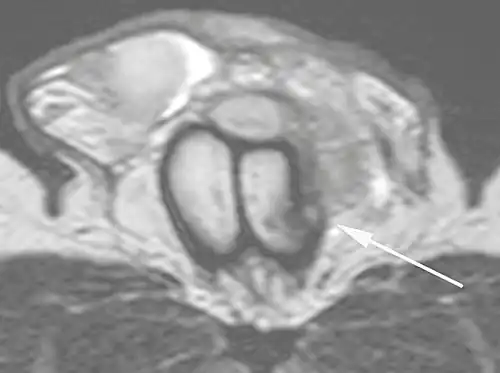

Ultrasound examination is able to depict the tunica albuginea tear in the majority of cases (as a hypoechoic discontinuity in the normally echogenic tunica). In a study on 25 patients, Zare Mehrjardi et al. concluded that ultrasound is unable to find the tear just when it is located at the penile base. In their study magnetic resonance imaging (MRI) accurately diagnosed all of the tears (as a discontinuity in the normally low signal tunica on both T1- and T2-weighted sequences). They concluded that ultrasound should be considered as the initial imaging method, and MRI can be helpful in cases that ultrasound does not depict any tear but clinical suspicions for fracture are still high. In the same study, authors investigated accuracy of ultrasound and MRI for determining the tear location (mapping of fracture) in order to perform a tailored surgical repair. MRI was more accurate than ultrasound for this purpose, but ultrasound mapping was well correlated with surgical results in cases where the tear was clearly visualized on ultrasound exam.[10] The advantage of ultrasound in the diagnosis of penile fracture is unrivaled when its noninvasive, cost-effective, and nonionising nature are considered.[11]

In the ultrasound examination, a lesion of the tunica albuginea presents as an interruption in (loss of continuity of) the echoic line representing it (Figure 4). Small, moderate, or broad hematomas demonstrate the extent of that discontinuity. Intracavernous hematomas, sometimes without the presence of a tunica albuginea fracture, can be observed when there is a lesion of the smooth muscle of the trabeculae surrounding the sinusoid spaces or the subtunical venular plexus.[2]

In 10–15% of penile traumas, there can be an accompanying urethral lesion. When blood is observed in the urethral meatus, contrast-enhanced evaluation of the urethra is necessary. In cases in which the ultrasound findings are inconclusive, the use of magnetic resonance imaging can facilitate the diagnosis and is recommended by various authors.[2]